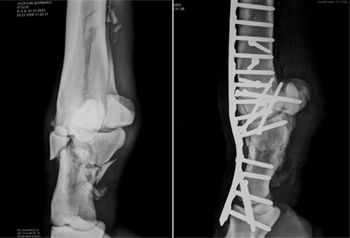

Kennett Square, Pa. -- Many patients leave caregivers with indelible memories, but none like this one.

Barbaro's eight-month stay at the University of Pennsylvania School of Veterinary Medicine's New Bolton Center had a dramatic effect on the work environment at the George D. Widener Hospital for Large Animals and other school facilities.